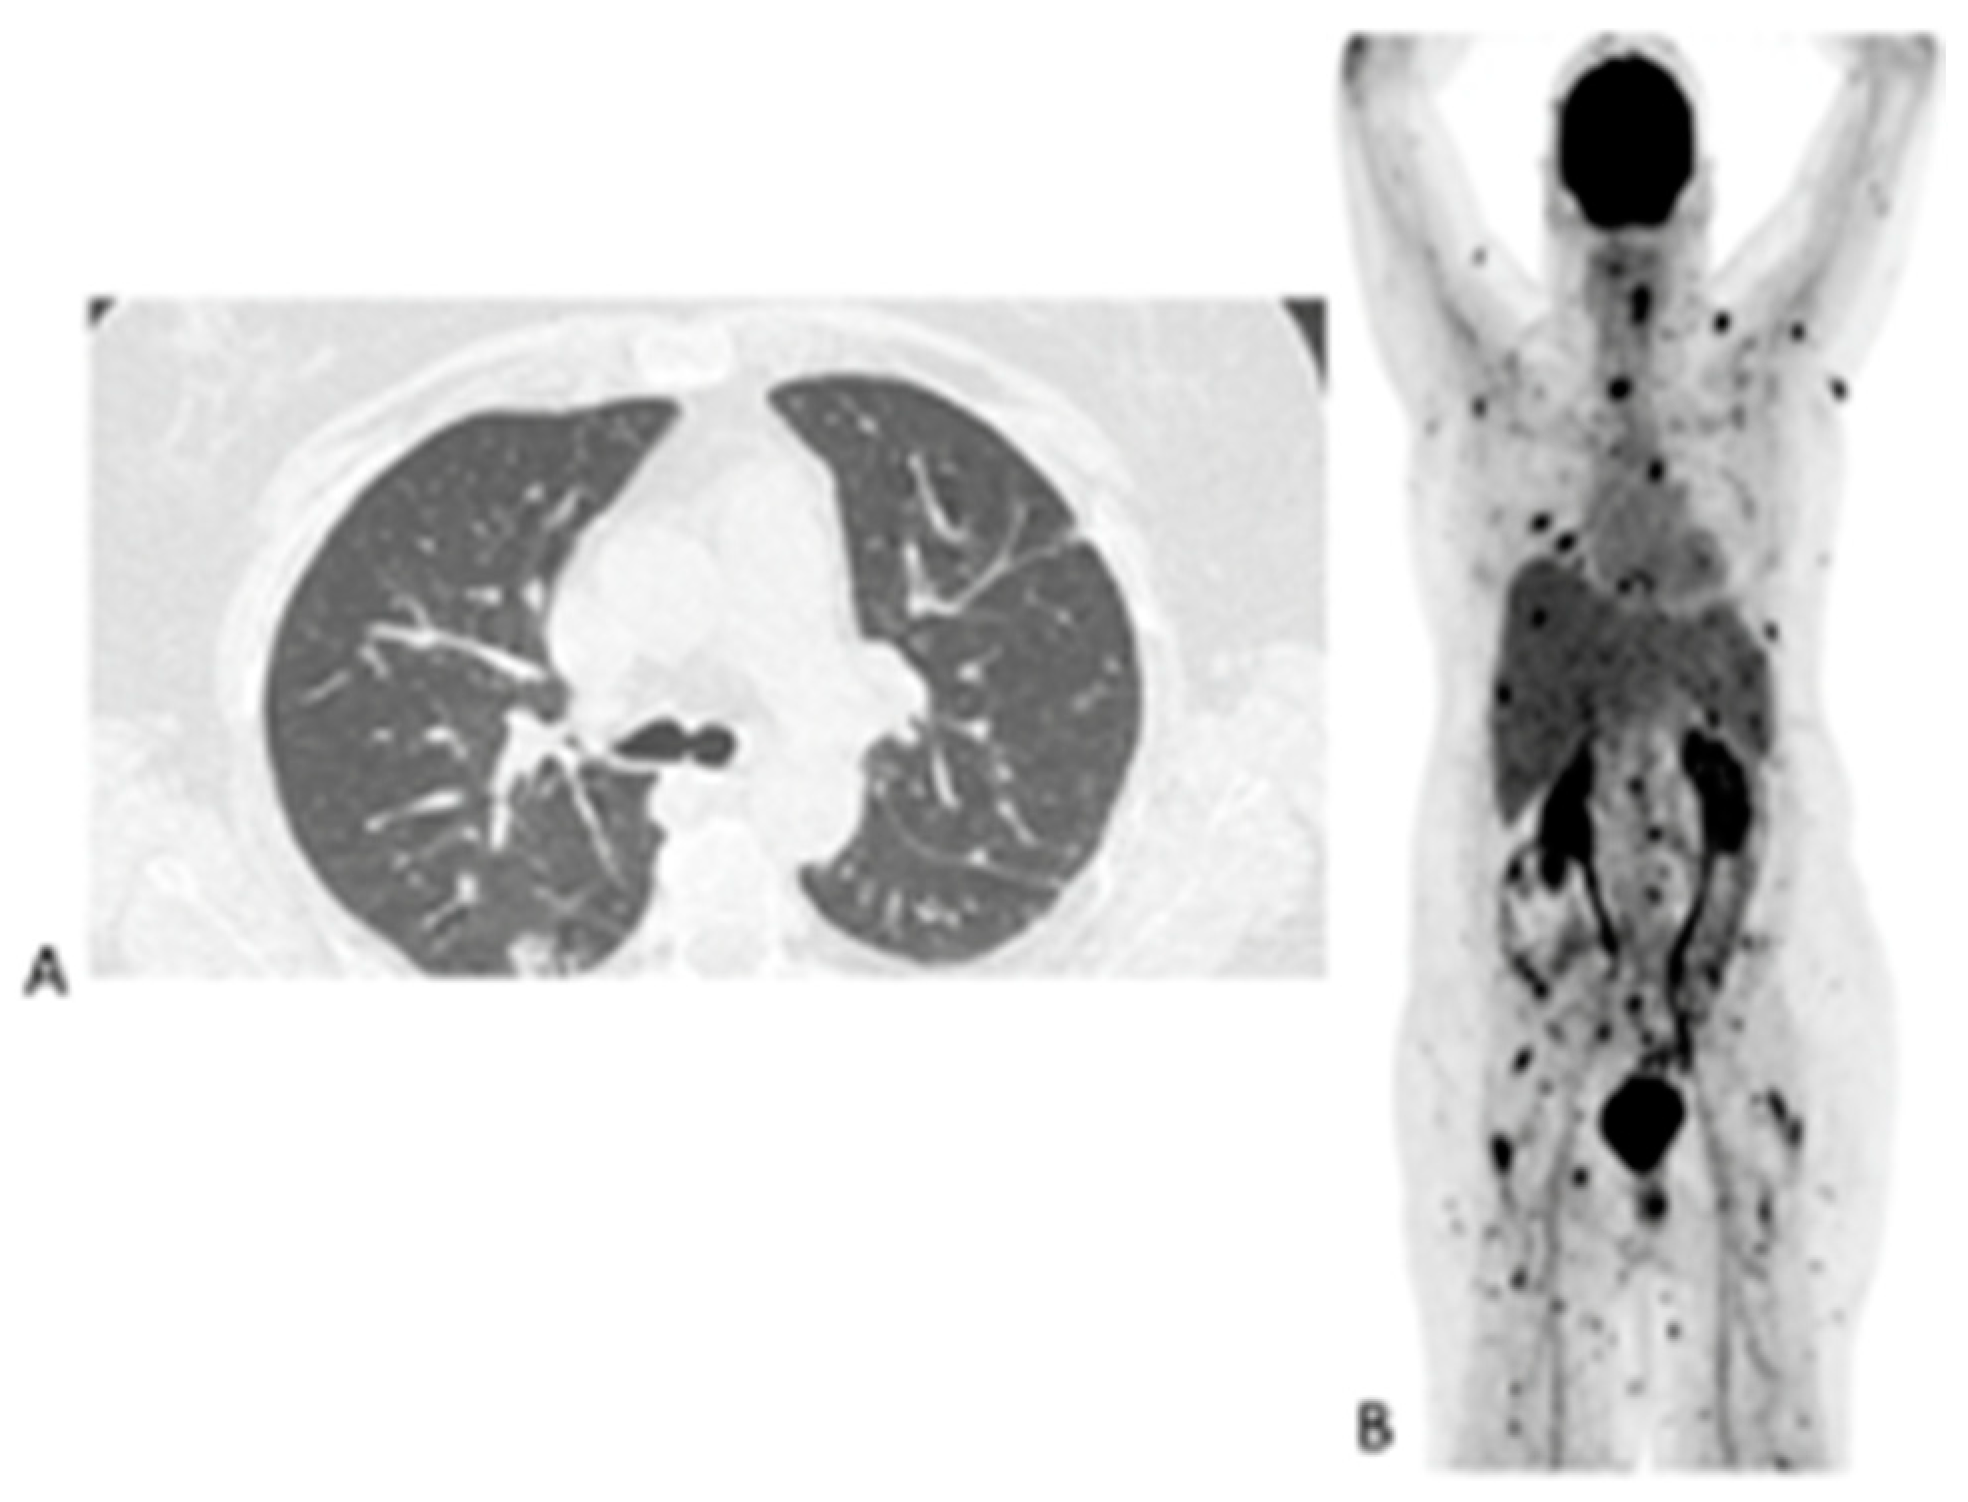

Of the 155 [18F]FDG PET/CT studies that were analyzed, 34 (22%) had no anatomy-based imaging (Table 3). Of the 34 [18F]FDG PET/CT studies that had no anatomy-based imaging, 28 (82.4%), were scans that were performed for the follow-up of IFI lesions that had been previously noted by previous imaging. The remaining four were two in patients being prepared for ASCT, and two in two patients for which [18F]FDG PET/CT had found metabolic activity in residual IFI lesions. Figure 2 shows a patient for which [18F]FDG PET/CT only was used to follow up because the IFI lesions could only be detected by the metabolic component of the study. Table 3 outlines the number of anatomy-based studies that were performed for each [18F]FDG PET/CT scan studied and the concordance between the [18F]FDG PET/CT and anatomy-based study at the site of the study.

Figure 2. Maximum intensity projection (MIP) of [18F]FDG images of a 10-year-old girl on chemotherapy for acute lymphocytic leukemia. She had a persistent fever unresponsive to antibiotics. HR CT not shown (was unremarkable). The initial study (A) revealed widespread, multiple, small, metabolically active foci in the muscles and esophagitis, which were later found to be due to Candida dubliniesis upon biopsy. The lesions were not detected by the corresponding CT of the [18F]FDG PET/CT study. A follow-up [18F]FDGPET/CT study (B) after 6 weeks of antifungal treatment showed a very good metabolic response, with a single residual focus in the right gluteus and the resolution of the esophagitis. No anatomy-based study was performed together with the follow-up [18F]FDG PET/CT study (B).